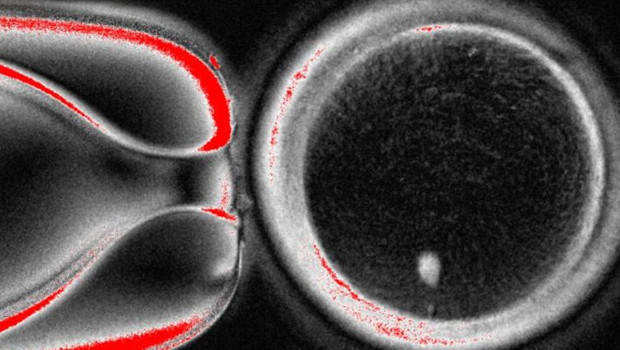

Araştırmacılar, bu yönteme “mitomeyoz” adını veriyor. Normalde vücudumuzdaki hücrelerde 46 kromozom bulunuyor, ancak sağlıklı bir yumurta hücresinin 23 kromozoma sahip olması gerekiyor. Yeni teknikle deri hücresinin çekirdeği, boşaltılmış bir yumurtaya aktarılıyor ve ardından hücre kendi kromozomlarının yarısını dışarı atıyor. Böylece normal bir yumurta hücresine benzer hale geliyor.

Ardından bu laboratuvar yumurtaları spermle döllenerek embriyo gelişimi başlatıldı. Araştırmada 82 yumurta oluşturuldu, bunlardan yaklaşık yüzde 9’u blastosist aşamasına kadar ilerledi. Bu oran düşük olsa da, tekniğin çalışabileceğini kanıtlayan ilk somut adım olarak değerlendiriliyor.